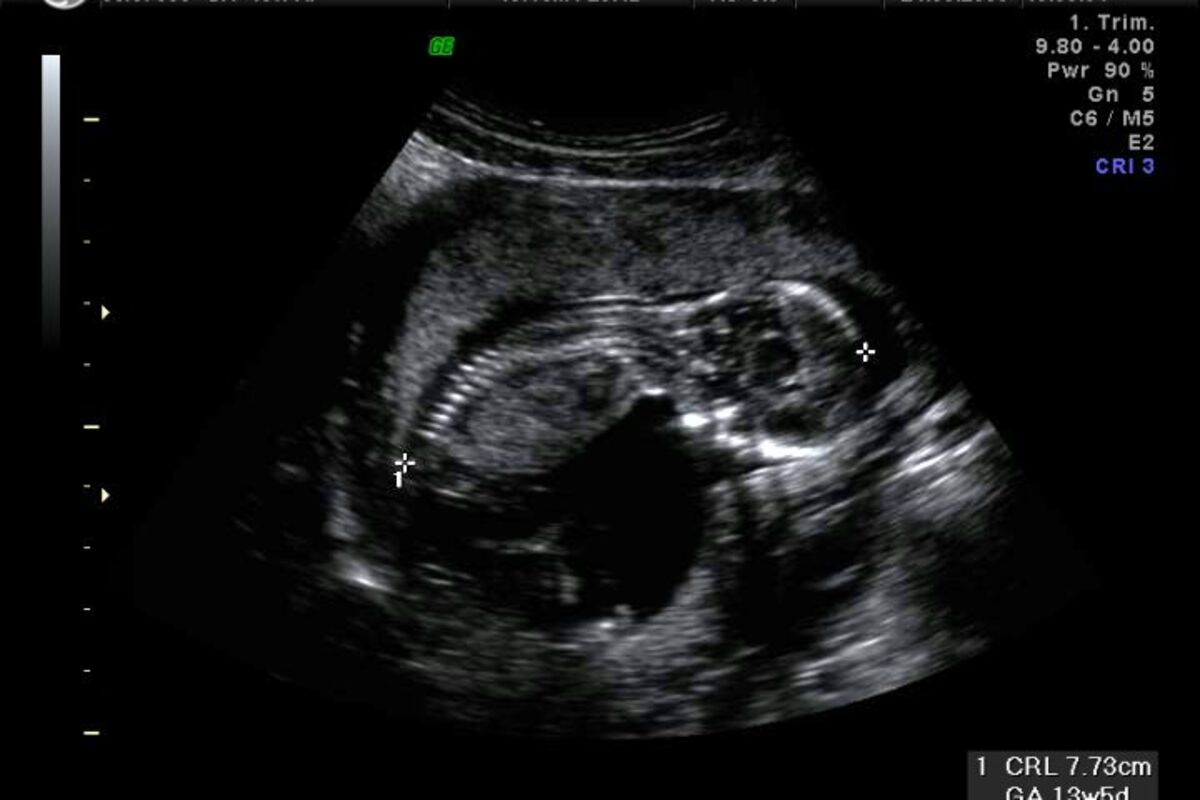

ultrazvuk, Foto: Kiwi.logix.cz

Posljednja riječ nauke, kada je u pitanju perinatalna medicina, testovi nazvani KANAT koji su u mogućnosti da utvrde razvoj mozga nerođene bebe, mogli bi se uskoro primjenjivati i u Kliničkom centru Crne Gore.

Ultrazvuk aparat koji se koristi za testiranje je standardni, četvorodimenzionalni, a upotrebljava se posebna sonda. Kurjak je kazao da nije toliko bitan kvalitet aparata, već je važnije iskustvo ljekara koji primjenjuje test.

On je naglasio značaj ultrazvuka u vođenju trudnoće, pomoću kojeg se otkrivaju abnormalnosti ploda i omogućava liječenje prije rođenja.